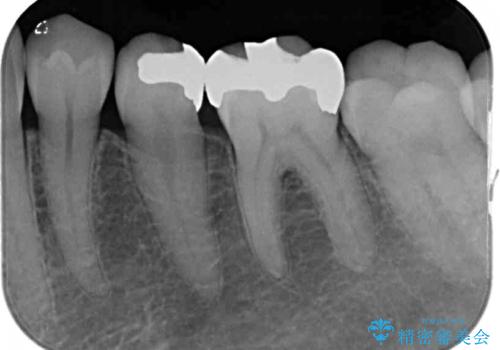

- 銀歯をセラミックにしたいとのことで来院された患者様です。

まず麻酔をして銀歯を外し、むし歯を除去し、形を整えて型取りします。

そして次の来院時、セラミックインレーを装着し、噛み合わせなどの調整を行います。

それを左右に分けて行いました。

インレーを装着するときは、唾液や血液による接着力の低下を避けるためにラバーダム防湿を行いました。